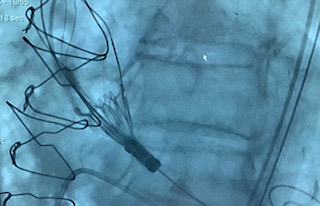

Alliberament d'una TAVI

Alliberament d'un TAV

Alliberament TAVI